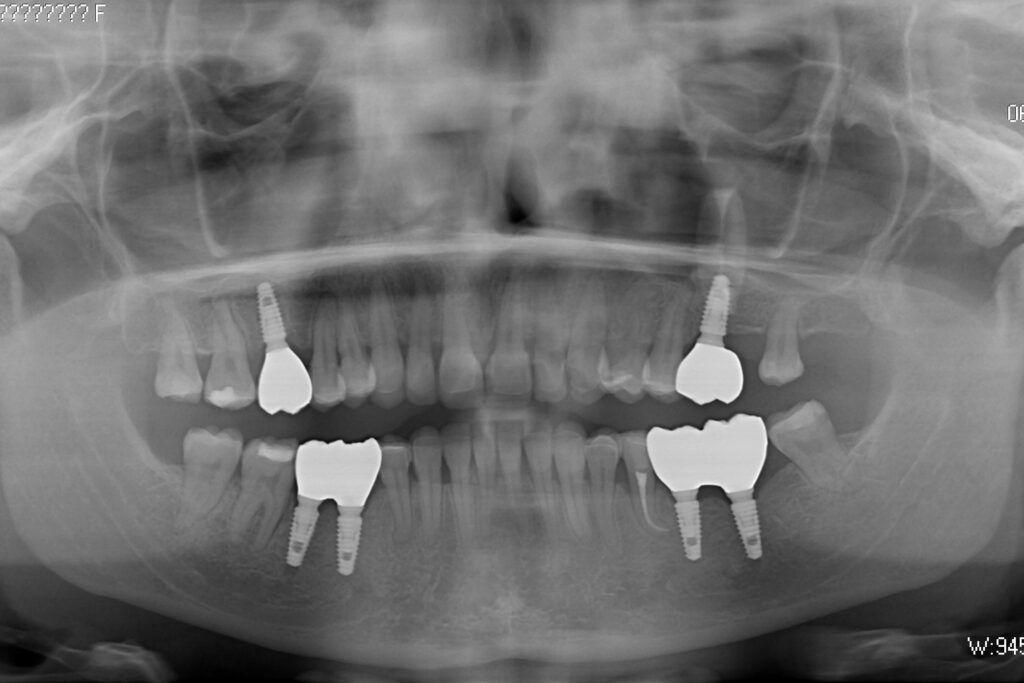

Этап имплантации и протезирования и результаты

Затем были установлены имплантаты Megagen AnyOne.

Спустя 3 месяца после установки имплантатов была произведена замена несостоятельных реставраций и пломб для избежания развития вторичного кариеса под винирами и коронками.

Сделано препарирование зубов на верхней и нижней челюстях с контролем глубины (0.7-0.8 мм) под керамические реставрации. Сняты оттиски с имплантатов.

Установлены временные виниры и коронки из пластика. Спустя 26 дней были зафиксированы керамические виниры и коронки на своих зубах и циркониевые коронки на имплантатах.